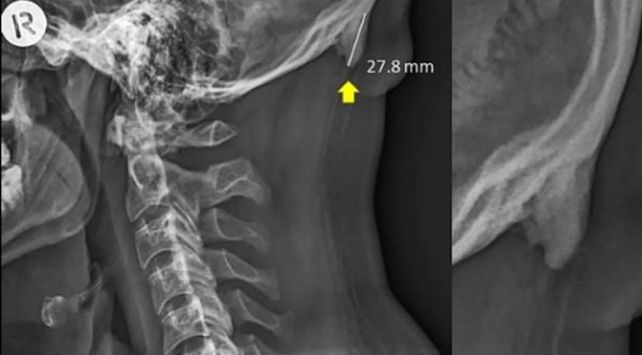

La estructura ósea trata de adaptarse para sostener mejor nuestra cabeza. La prueba está en las imágenes de rayos X publicadas por investigadores australianos. La cabeza de adulto promedio puede pesar alrededor de 5 kilogramos.